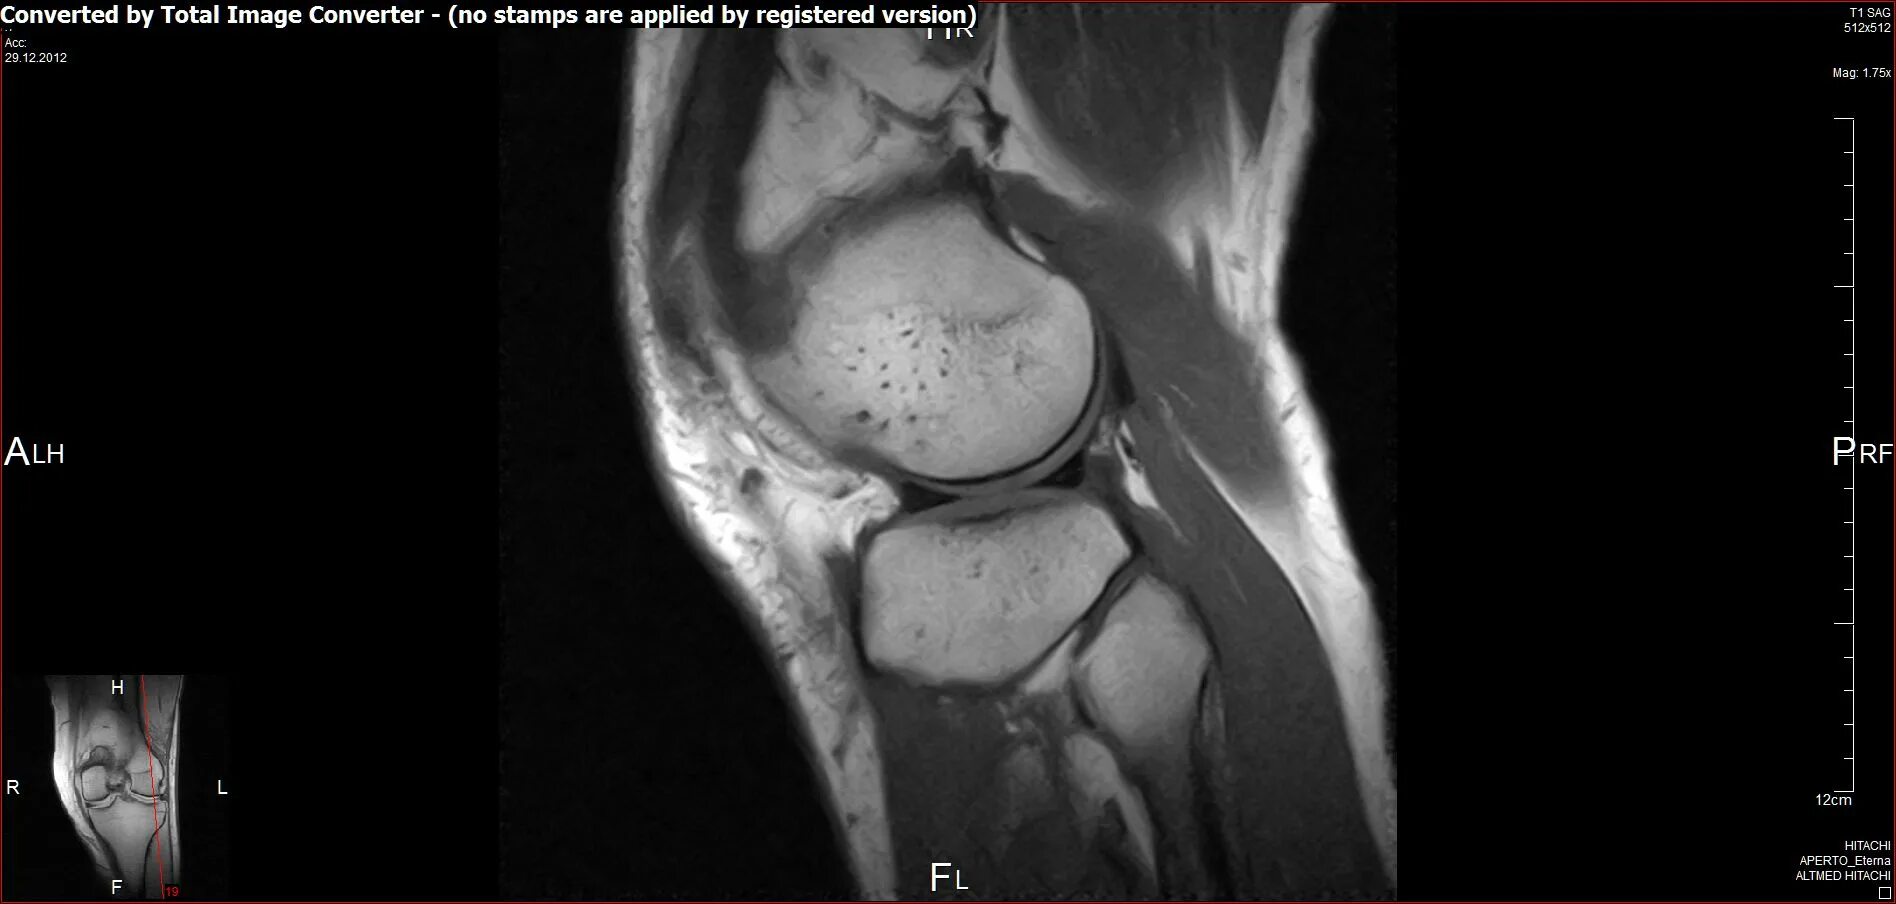

Мрт суставов кемерово